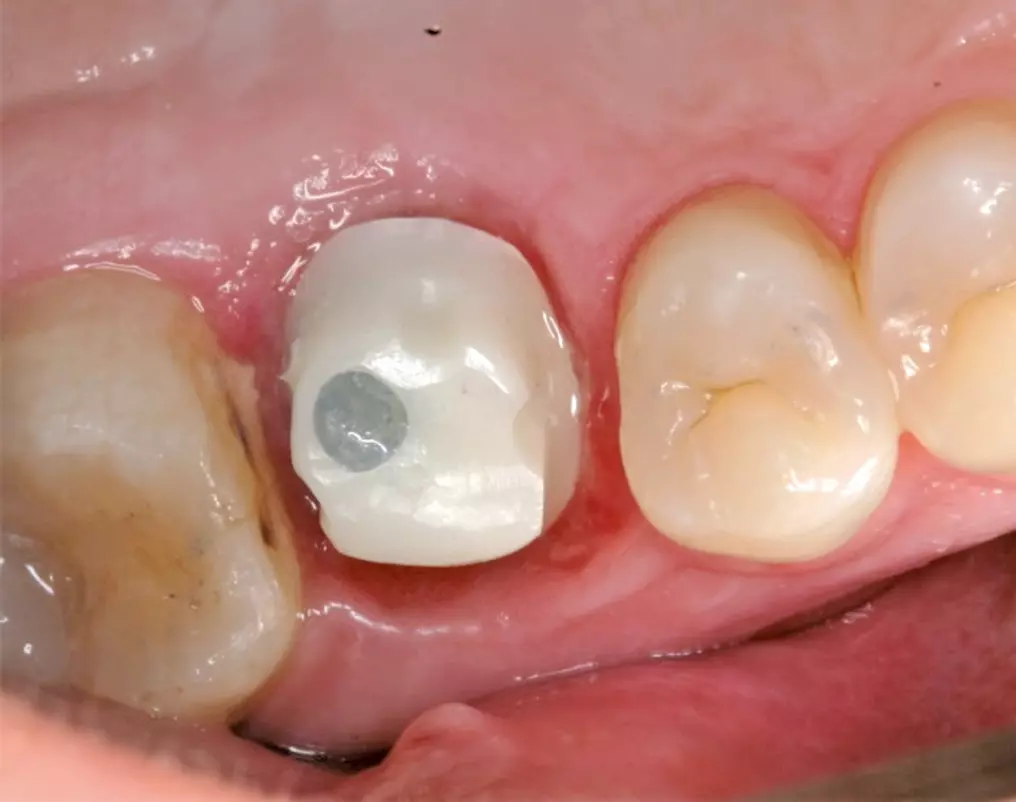

Verschraubung der mit dem Abutment verklebten Restauration direkt im Implantat

Ein weiterer Vorteil ist darin zu sehen, dass nur eine Verschraubungseinheit vorliegt, deren Schraubenkopf zudem tief an der Basis des Abutments angeordnet ist und einen relativ kleinen Durchmesser aufweist. Damit lässt sich der okklusale Zugang in gleicher Weise wie oben erwähnt verschließen und ein günstiger kosmetischer Effekt erzielen (Abb. 5a-d).